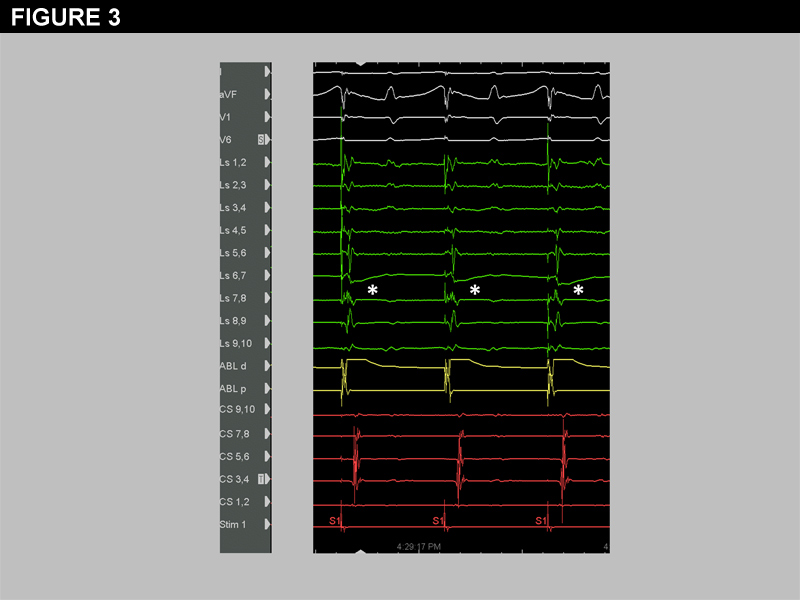

After subsequent isolation of the right pulmonary veins, the spiral catheter was replaced in the LSPV to assess for acute reconnection. Although the LSPV EGMs remained largely unchanged (Figure 2a), high output pacing (10mA, 2.0ms) from electrodes on the anterior margin of the vein now captured the LA, shown in Figure 2b. No spontaneous pulmonary vein potentials were seen in the LSPV.

The differential diagnosis for LA capture after apparent successful isolation of the LSPV includes: 1) subtle or unidirectional acute reconnection, 2) far-field capture of the left atrial appendage or 3) connection of the left pulmonary veins to the LA via the ligament of Marshall.